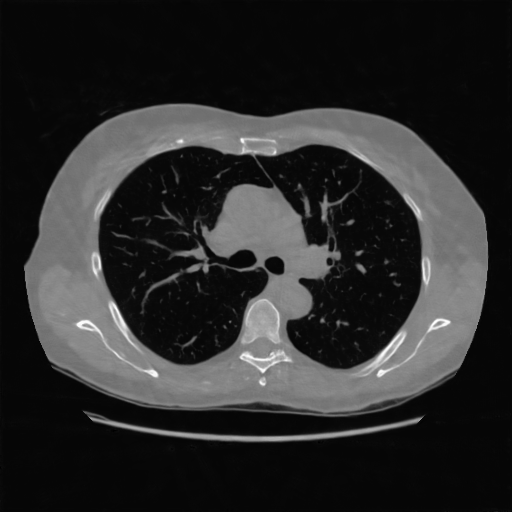

IV-C Few-View CT Reconstruction

In this section, the reconstruction performance of our proposed framework under few-view conditions will be tested. For the parallel and fan beam geometry, the number of views increases from to , uniformly distributing from to and to respectively. Such settings provide a complete benchmark of reconstruction performance, ranging from extremely sparse to relatively complete, full-view CT reconstruction. The experiment results are shown in Fig.5. Additionally, the ground truth, few-view ( views), and full-view ( views) CT reconstruction results of different methods are shown in the first and third rows of Fig.7 (parallel-beam, LIDC-IDRI dataset), and Fig.8 (fan-beam, LIDC-IDRI dataset).

(a) Ground Truth

43.87dB/0.96

(b) ASD-POCS

47.96dB/0.97

(c) RBP-DIP

34.46dB/0.84

(d) DIP

26.63dB/0.93

(e) MED50

29.03dB/0.95

(f) RED-CNN